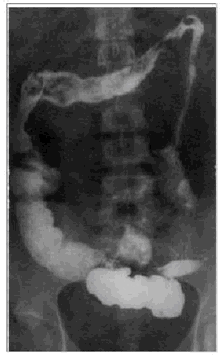

(5). 提示:体检:T37.6℃,P88次/分,BP120/82mmHg。营养状态欠佳,皮肤巩膜无黄染,颈部及锁骨上窝、腋窝等浅表淋巴结无肿大,轻度贫血貌,脱水貌。双肺检查正常。心音纯,心律规整,心率88次/分。腹部平软,肝脾未及,左、右下腹压痛,肠鸣音亢进,12次/分双下肢无水肿。辅助检查:血常规Hb92g/L,大便常规为粘液脓血便,红细胞7-10个/HP,白细胞10-15个/HP。大便阿米巴滋养体与包囊阴性。便细菌培养阴性。血K3.0mmol/L,Na130mmol/L,CI97mmol/L。血浆总蛋白(TP)58g/L,白蛋白(A)28,球蛋白(G)30g/L。钡餐检查如图。有关该患者的治疗正确的有

A. 充分休息

B. 予以肠外营养支持

C. 可使用氢化可的松治疗

D. 纠正贫血及水电解质紊乱

E. 水氧酸偶氮磺胺吡啶为首选试用药

F. 控制饮食,增加蛋白质供应,如增加牛奶的摄入

G. 首选的术式为结肠大部切除,回肠及乙状结肠造

H. 治疗该病的最有效的手术是:结、直肠全部切除,永久性末端回肠造口